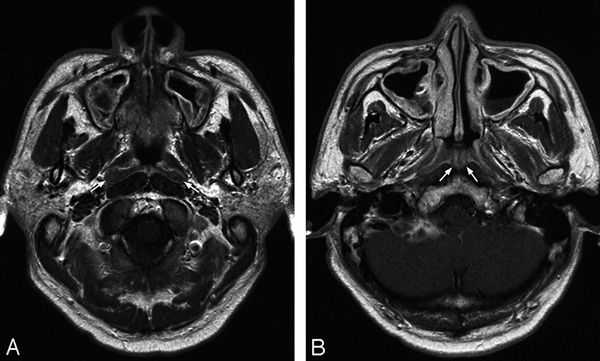

Магнитно-резонансная томография

МРТ придаточных пазух особенно важна в диагностике осложнений, особенно, распространения инфекции в полость черепа.

Стандартное исследование предполагает корональные Т1- и Т2-зависимые МРТ

изображения. Подавление сигнала от жира рекомендуется, но не является обязательным. Необходимость других проекций и импульсных последовательностей диктуется конкретной клинической ситуацией. При подозрении на опухоль рекомендуется исследование с контрастированием.

Жидкость, ретенционные кисты и отёчная слизистая гиперинтенсивны на Т2-зависимых МРТ изображениях. Т1-зависимые МРТ изображения иногда вносят ясность, так как ретенционные кисты могут быть светлее за счет повышенного содержания белка. Жидкость, напротив, обычно темнее воспаленной слизистой.

Главным недостатком МРТ является плохая визуализация костных границ синусов. Кроме того, отмечается высокий уровень ложно-положительных результатов. Небольшой гиперинтенсивных сигнал от слизистой на Т2-зависимых томограммах при отсутствии клинической симптоматики наблюдается часто у здоровых лиц. Таким образом, при неосложненных острых синуситах МРТ не является обязательной диагностической процедурой.

Этмоидит. МРТ придаточных пазух носа. Поперечная плоскость (увеличение), Т1-зависимое МРТ изображение.